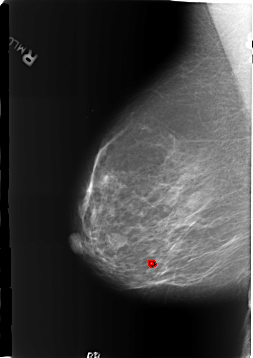

B_3186_1.RIGHT_MLO

FILE: B_3186_1.RIGHT_MLO.OVERLAY

TOTAL_ABNORMALITIES 1

ABNORMALITY 1

LESION_TYPE CALCIFICATION TYPE LUCENT_CENTER DISTRIBUTION N/A

ASSESSMENT 2

SUBTLETY 4

PATHOLOGY BENIGN_WITHOUT_CALLBACK

TOTAL_OUTLINES 1

BOUNDARY